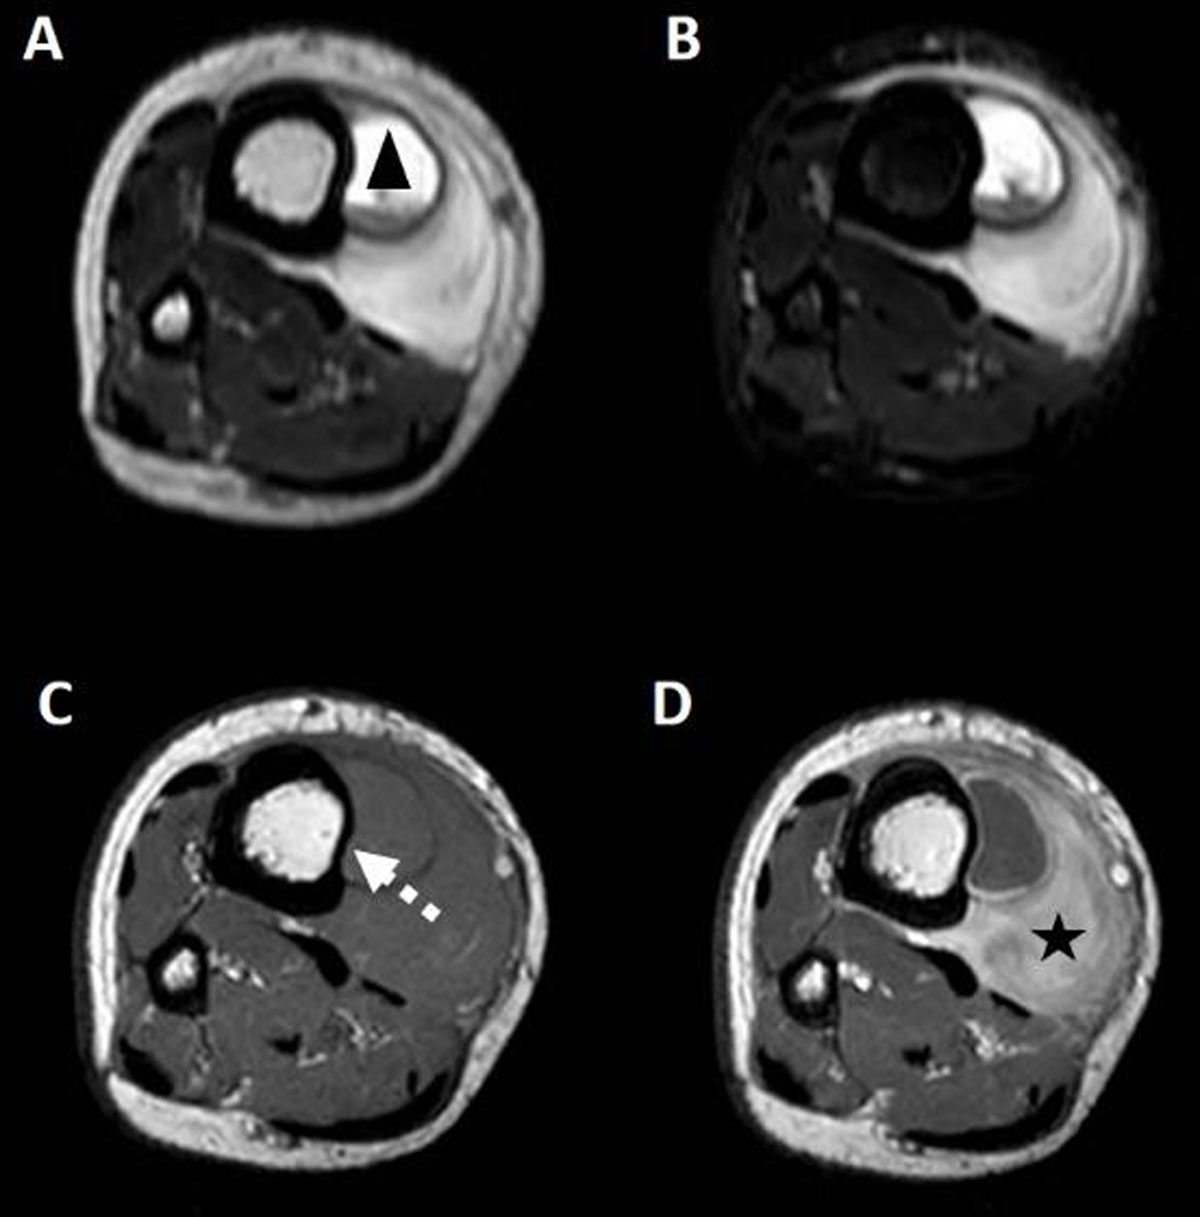

Radiographs (Figure 1) demonstrated a soft tissue swelling on the medial side of the tibial shaft outlined by a thin calcified rim (arrowheads). A smaller, similar lesion could be seen more cranially (arrow). Ultrasound (US) (Figure 2A-C) showed a subperiosteal collection (circle) with an internal fluid-fluid level (arrow) as well as calcification of the surrounding periosteum. The calcified periosteum is surrounded by a heterogeneous, vascularized soft tissue cuff (arrowheads). MRI (Figure 3A-D) demonstrated a subperiosteal collection with signal properties of a chronic hematoma (triangle): T1/T2-isointense in the periphery of the lesion but T1-iso/T2-hyperintense in the centre (Figure 3C and 3A, respectively, for T1- and T2-weighted imaging). Moreover, there was the additional finding of a T2-hyperintense, T1-isointense, fat-poor (Figure 3B), enhancing tissue (star in Figure 3D), located medially and posteriorly with respect to the hematoma, corresponding to the described soft tissue cuff on US. These MRI features were suggestive of a plexiform neurofibroma of the saphenous nerve, that has caused an ossifying subperiosteal hematoma due to chronic erosion of the tibial cortex. Note the smooth cortical thinning on MRI (dashed arrow), the mass effect exerted on the tibialis posterior and flexor digitorum muscles as well as the surrounding soft tissue oedema.

Figure 3